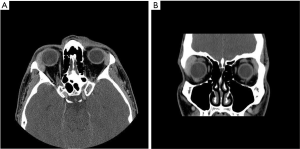

As gastric MALT lymphoma is often a multifocal disease, the radiation target volume should include the entire stomach, even in cases where the disease may appear to be confined to one region of the stomach. Lymph nodes are only included if they are suspected to be involved with the disease. In older RT series, patients were treated with extensive RT fields to the entire abdomen (5,40,41). Long term outcomes reported by Wirth et al. on behalf of the International Extranodal Lymphoma Study Group (IELSG) revealed that radiation field size and RT dose was not associated with increased treatment failure among 102 gastric MALT lymphoma patients in which 41 received RT to the whole abdomen and 61 were treated to the stomach and involved nodes (5). The German Study Group on Gastrointestinal Lymphoma performed stage adaptive RT field reductions over the course of 3 prospective trials for gastric MALT lymphoma patients without loss of local control but with lesser frequency of treatment related toxicities (42). Current recommendations from ILROG suggest that the CTV should encompass the stomach from the gastroesophageal junction to beyond the duodenal bulb as well as any pathologically involved nodes (15). Modern technology should be used to reduce doses to neighboring normal structures, including the heart, kidneys and spleen (Figure 1). As the stomach is subject to significant motion due to peristalsis, respiratory motion and variations in stomach filling, techniques and procedures directed at accounting for organ motion are essential. Patients should have NPO status at least 6 hours prior to therapy, four dimensional (4D) CT simulation or DIBH techniques should be used for treatment and PTV margins should be adjusted according to the image guidance technique utilized (Figure 1). With DIBH and daily CT image guidance, 1.0–1.5 cm margins are often used (43). With free breathing treatment and 2D imaging alignment to bony anatomy however, margins of 2.2 cm or greater have been shown to be necessary to achieve adequate PTV coverage (44). DIBH technique has been shown to be a promising strategy to reduce unintended radiation to the heart when treating gastric MALT lymphoma patients (45,46).